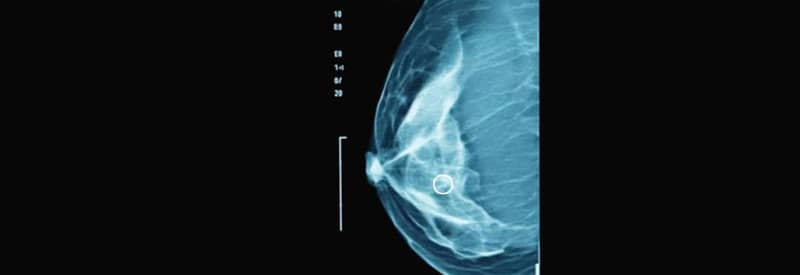

The story of mammography spans more than a century, beginning in 1913 with the world’s first mammographic images. Since then, the field has advanced through major milestones, from the introduction of screening programs and stereotactic biopsy to the emergence of digital imaging, tomosynthesis, and AI-driven tools.

Stereotactic breast biopsy, which uses three dimensional coordinates to sample non-palpable lesions, meaning small abnormalities that cannot be felt during a physical exam, was pioneered in Sweden alongside early screening programs. Karolinska Institutet in Stockholm led the world in clinical application, thanks to innovators Sven K. Franzén and Josef Zajicek, both renowned pathologists who advanced breast cancer diagnostics. The first stereotactic biopsy table was built in the early 1980s, reducing unnecessary surgery for benign findings, which are noncancerous tissue changes. The technique quickly spread internationally, with U.S. adoption in 1986 and 1987 directly influenced by Swedish expertise.

In 1913, German physician Albert Salomon captured the world’s first mammographic images by X-raying surgically removed breasts to study cancerous tissue. His pioneering work revealed how different breast tumors appeared on X-ray and how they spread to lymph nodes, laying the foundation for modern breast imaging.